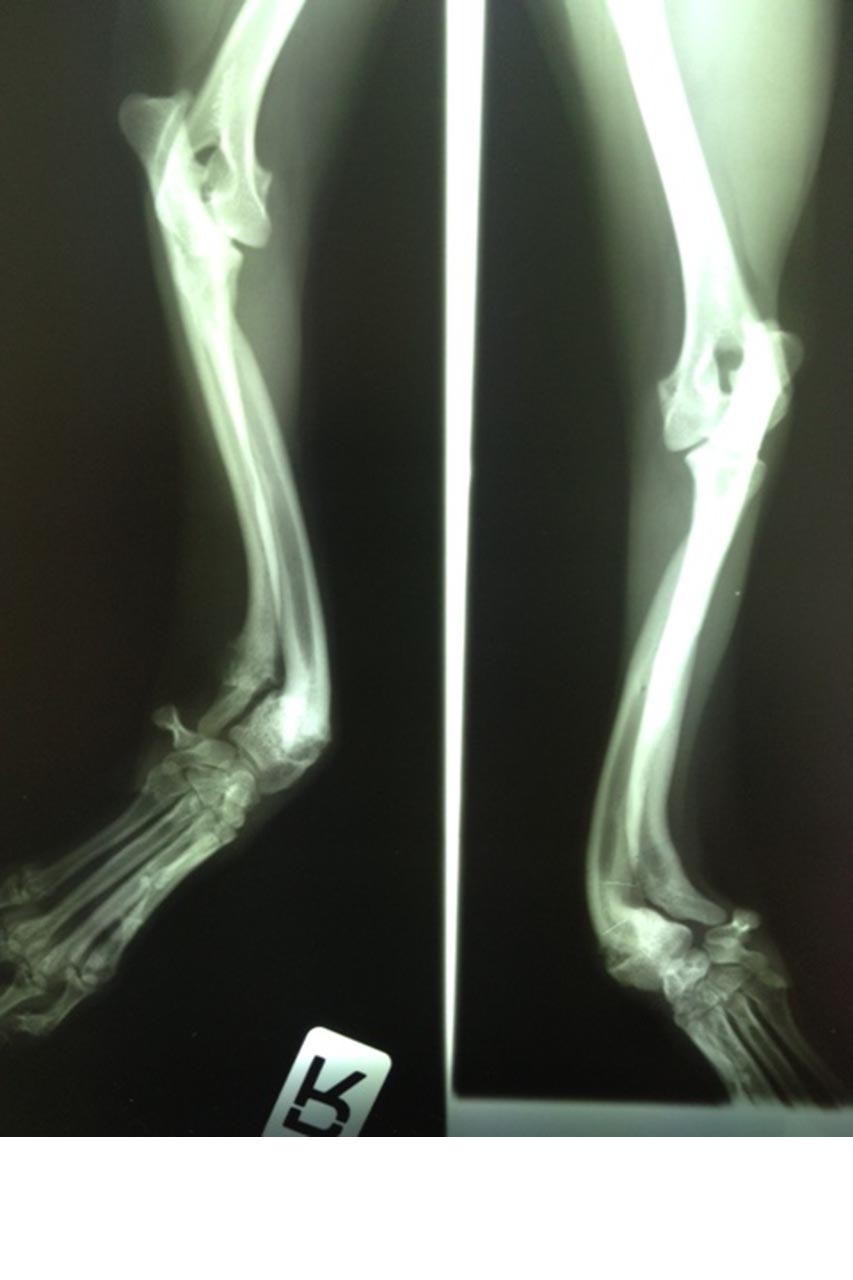

2008: Schlechter Start2018 - Auch schwere Fälle werden von uns behandelt

Nach und nach erfuhren wir, dass seit Monaten kein Tierarzt mehr gekommen war, denn die Zahlungen waren erst schleppend verlaufen und blieben dann ganz aus. Selbst für ausreichende Schmerzmedikamente war kein Geld vorhanden gewesen.

Wir haben in den vergangenen Jahren nicht nur eine sehr engagierte niedergelassene Tierärztin für die regelmäßige Betreuung unserer Tiere gewinnen können, sondern uns auch ein Netzwerk mit spezialisierten Tierärzten aufgebaut: Chirurgen, ein Herzspezialist, Augenspezialisten und mehrere Tierärzte, die uns bei unseren umfangreichen Kastrationsaktionen unterstützen.

Viele aufwendige Operationen bei Knochenproblemen ließen wir durchführen. Wir haben uns immer von der Notwendigkeit und nicht von den Kosten leiten lassen. Felipa mit ihren verwachsenen Pfötchen ist sicher noch vielen in Erinnerung. Als die Rechnungen sich bei ihr auf über 5.000 Euro summierten, haben wir aufgehört mitzurechnen. Zum Glück sind das Ausnahmen. Dennoch waren es im Laufe der letzten 10 Jahre viele schwere Fälle, denen wir mit teuren Behandlungen wieder ein schönes Leben ohne Leiden verschafft haben.